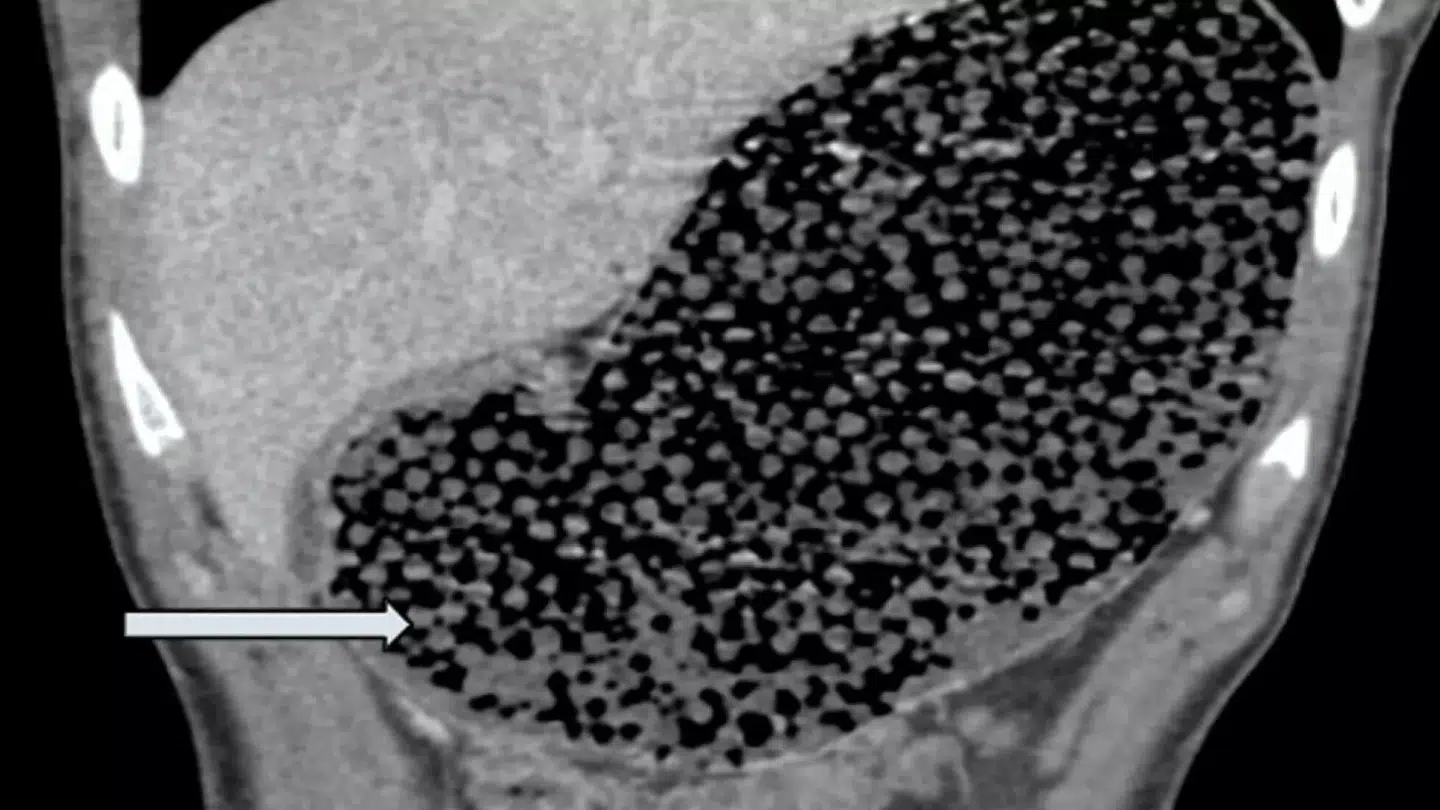

I CT-scanningen af drengen viste der sig »utallige små, runde perler i hele mave-tarmregionen«, og her fik lægerne fjernet mellem 50 og 70 af perlerne gennem en såkaldt gastroskopi.